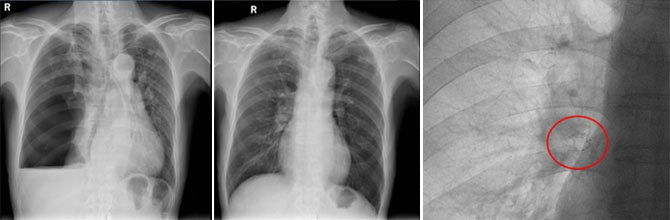

左图:入院前右侧液气胸,右肺压缩约90%。 中图:出院10天后,门诊复诊,右肺完全复张。 右图:红色圈中放大可见右肺下叶置入EBV活瓣。

2025年12月22日,樊伯康复出院。十天后门诊复查,他精神矍铄,胸片显示气胸未再复发。